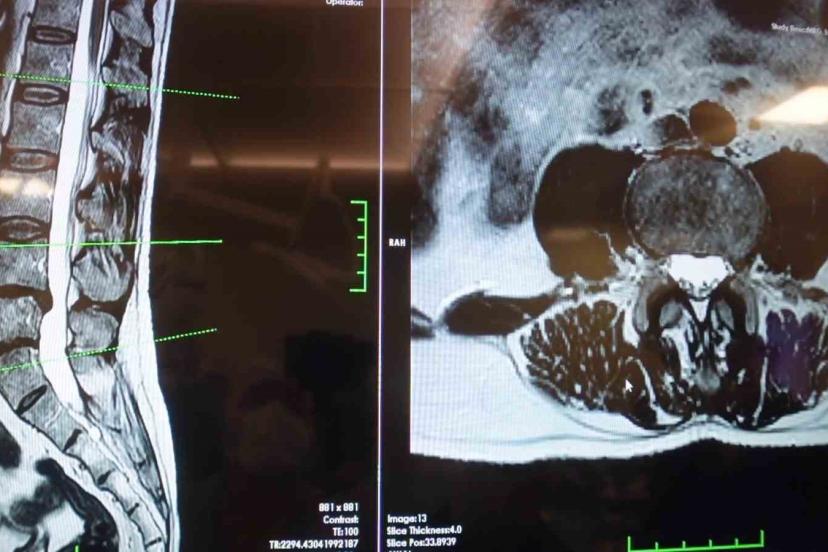

Elazığ Fırat Üniversitesi Hastanesi Beyin ve Sinir Cerrahisi Anabilim Dalı Başkanı Prof. Dr. Fatih Serhat Erol, "Bel fıtığının önemli bir hastalık olduğunun altını çizerek bel ağrılarının büyük bir kısmının bel fıtığından değil de mekanik bel ağrısından kaynaklıdır" dedi.

Elazığ Fırat Üniversitesi Hastanesi Beyin ve Sinir Cerrahisi Anabilim Dalı Başkanı Prof. Dr. Fatih Serhat Erol, bel fıtığı hastalığı hakkında açıklamalarda bulundu. Beyin ve sinir cerrahisi pratiğinde sık karşılaşılan hasta gruplarından birinin omurga hastaları olduğunu belirten Prof. Dr. Erol, "Boyun ve sırt omurlarının yanı sıra en çok bel bölgesiyle ilgili sorunlar görülüyor. Bel fıtığı önemli bir hastalıktır. Bel ağrılarının büyük bir kısmının bel fıtığından değil, mekanik bel ağrısından kaynaklanıyor. Mekanik bel ağrısının kaslar, eklemler, iskelet sistemi ve bu yapıları birbirine bağlayan bağların uzun süreli zorlanması sonucu ortaya çıkmaktadır. Bu durumun hastalarda şiddetli bel ağrısına neden olabilir. Mekanik bel ağrısının bel fıtığı ile karıştırılmaması gerekiyor. Bel fıtığına kıyasla mekanik bel ağrıları çok daha sık görülüyor. Bir diğer önemli hasta grubu ise omurilik kanal darlığı olan hastalardır. Bu hastalıkta dejeneratif süreçler sonucunda omurilik kanalında ve sinir köklerinin geçtiği kemik kanallarda daralma ve kireçlenme meydana geliyor. Bu durumun omurilik ve sinir köklerinde sıkışmaya yol açar. Hastaların ayakta dururken ya da yürürken bel, kalça ve bacaklara yayılan şiddetli ağrılar hissettiğini, yürüyüş mesafesi arttıkça oturup dinlenme ihtiyacı duyarlar. Tedavi sürecinin doğru tanıya göre belirleniyor. Bel ve bacak ağrısı şikayeti olan hastaların mutlaka bir beyin ve sinir cerrahisi uzmanına başvurması gerekiyor. Hastaların şikayetlerinin dinlenmesi, gerekli muayene ve tetkiklerin yapılmasının ardından hastalıkların birbirinden ayırt edilebildiğini ve buna uygun tedavi planının oluşturulur" cümlelerini kullandı.